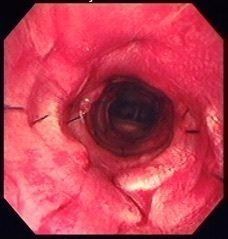

原因不明の犬の難病……気管がつぶれて呼吸ができなくなる『気管虚脱』とは